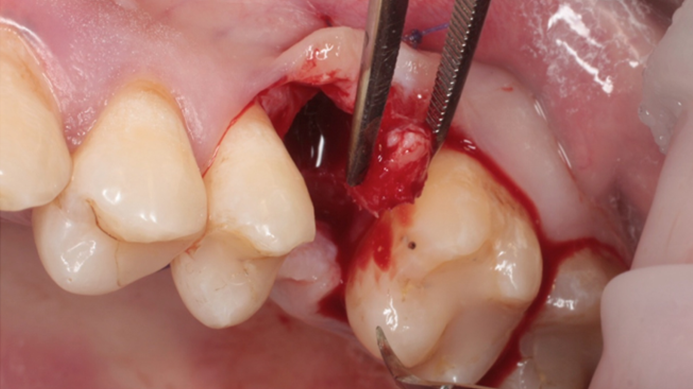

Clinical case: # 46 implant placement & GBR using i-Gen membrane for significant vertical resorption & mixed bone defect

- Courtesy of Dr. Iulian Filipov, Romania -

AnyRidge, mandibular posterior, i-Gen, resorption, bone defect, bone regeneration, space management, #46, GBR, Dr. Iulian Filipov